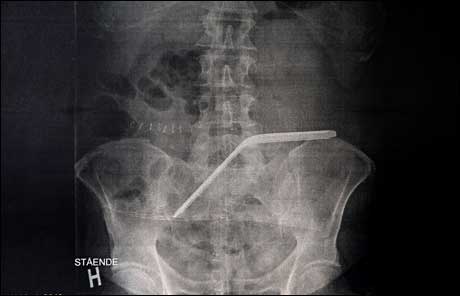

The kind of flexible sponge left inside this patient. Photo: Ole Åsheim, Nordlys.

This week one of the worst cases of retained surgical instruments in Norway was unraveled. A patient saw his five operations for colon cancer in a year turn to six, when it was discovered the surgeon had left behind a 20 cm long flexible sponge. The unique aspect of it however, was the patient’s reaction.

The patient had had a colostoma for a year and was looking forward to getting his colon tucked back in and reconnected. About a week after the operation he had a fever, and on returning to the hospital an x-ray revealed the retained sponge. But that’s not the whole story. Not only had the sponge count gone wrong, but it was discovered that a radiologist had noted the foreign body on a postop x-ray report, but no one had acted on it.